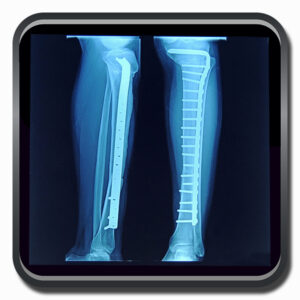

Algumas Cirurgias Complexas realizadas por profissionais da COFIB: